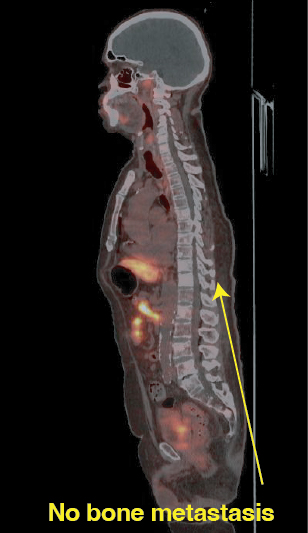

Cancer widely spread to lungs, bones, and lymph nodes

Precision imaging using advanced modalities such as PSMA PET-CT

Accurate identification of disease spread

Significant reduction in bone lesions